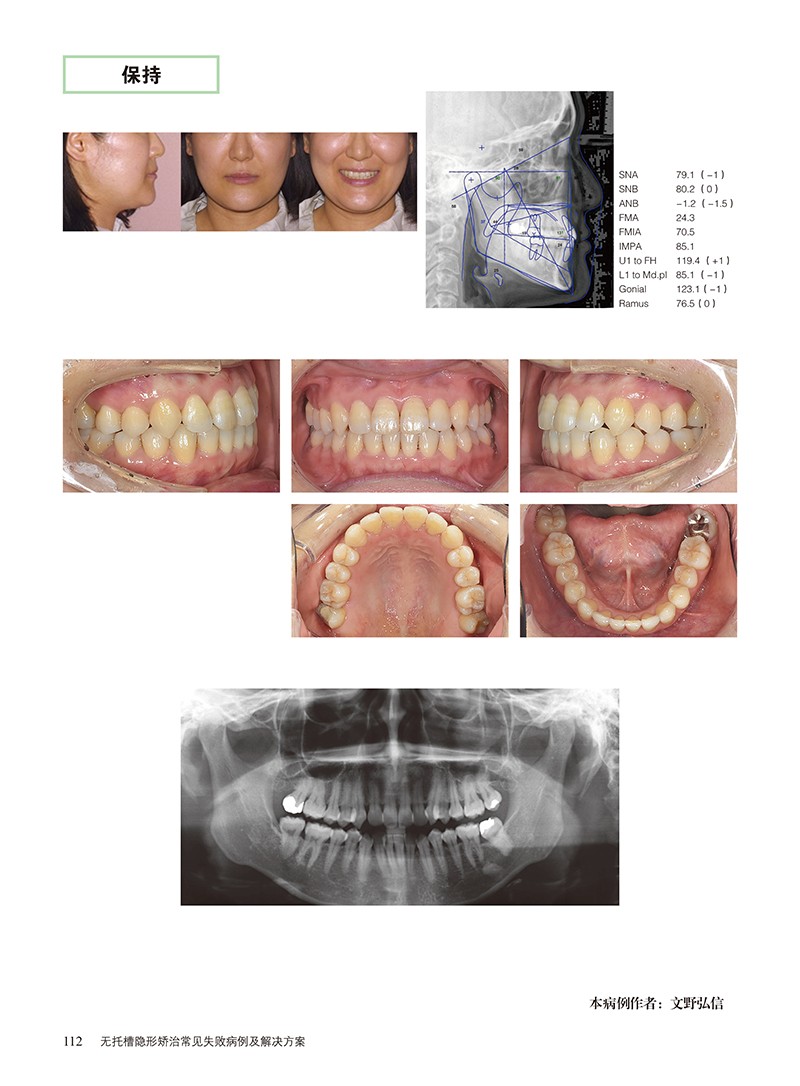

無托槽隱形矯正法與以往的矯正法有不同的特點,如果沒有正確的知識和技能,會招致各種各樣的麻煩和失敗。 本書整理了矯正失敗的相關知識和經驗,將失敗的機制和有效的恢復方法系統化。 通過找到失敗的原因,在能够滿足患者的要求的基礎上進行適當的治療。 本書分享了31個失敗的病例,介紹了矯正治療中常見的疑點和難點,並提供了相應的解決方案。 我們希望本書對廣大讀者的臨床實踐有所幫助,也希望最終誕生的這種應用電腦輔助科技的治療方法能够朝著正確的方向發展。